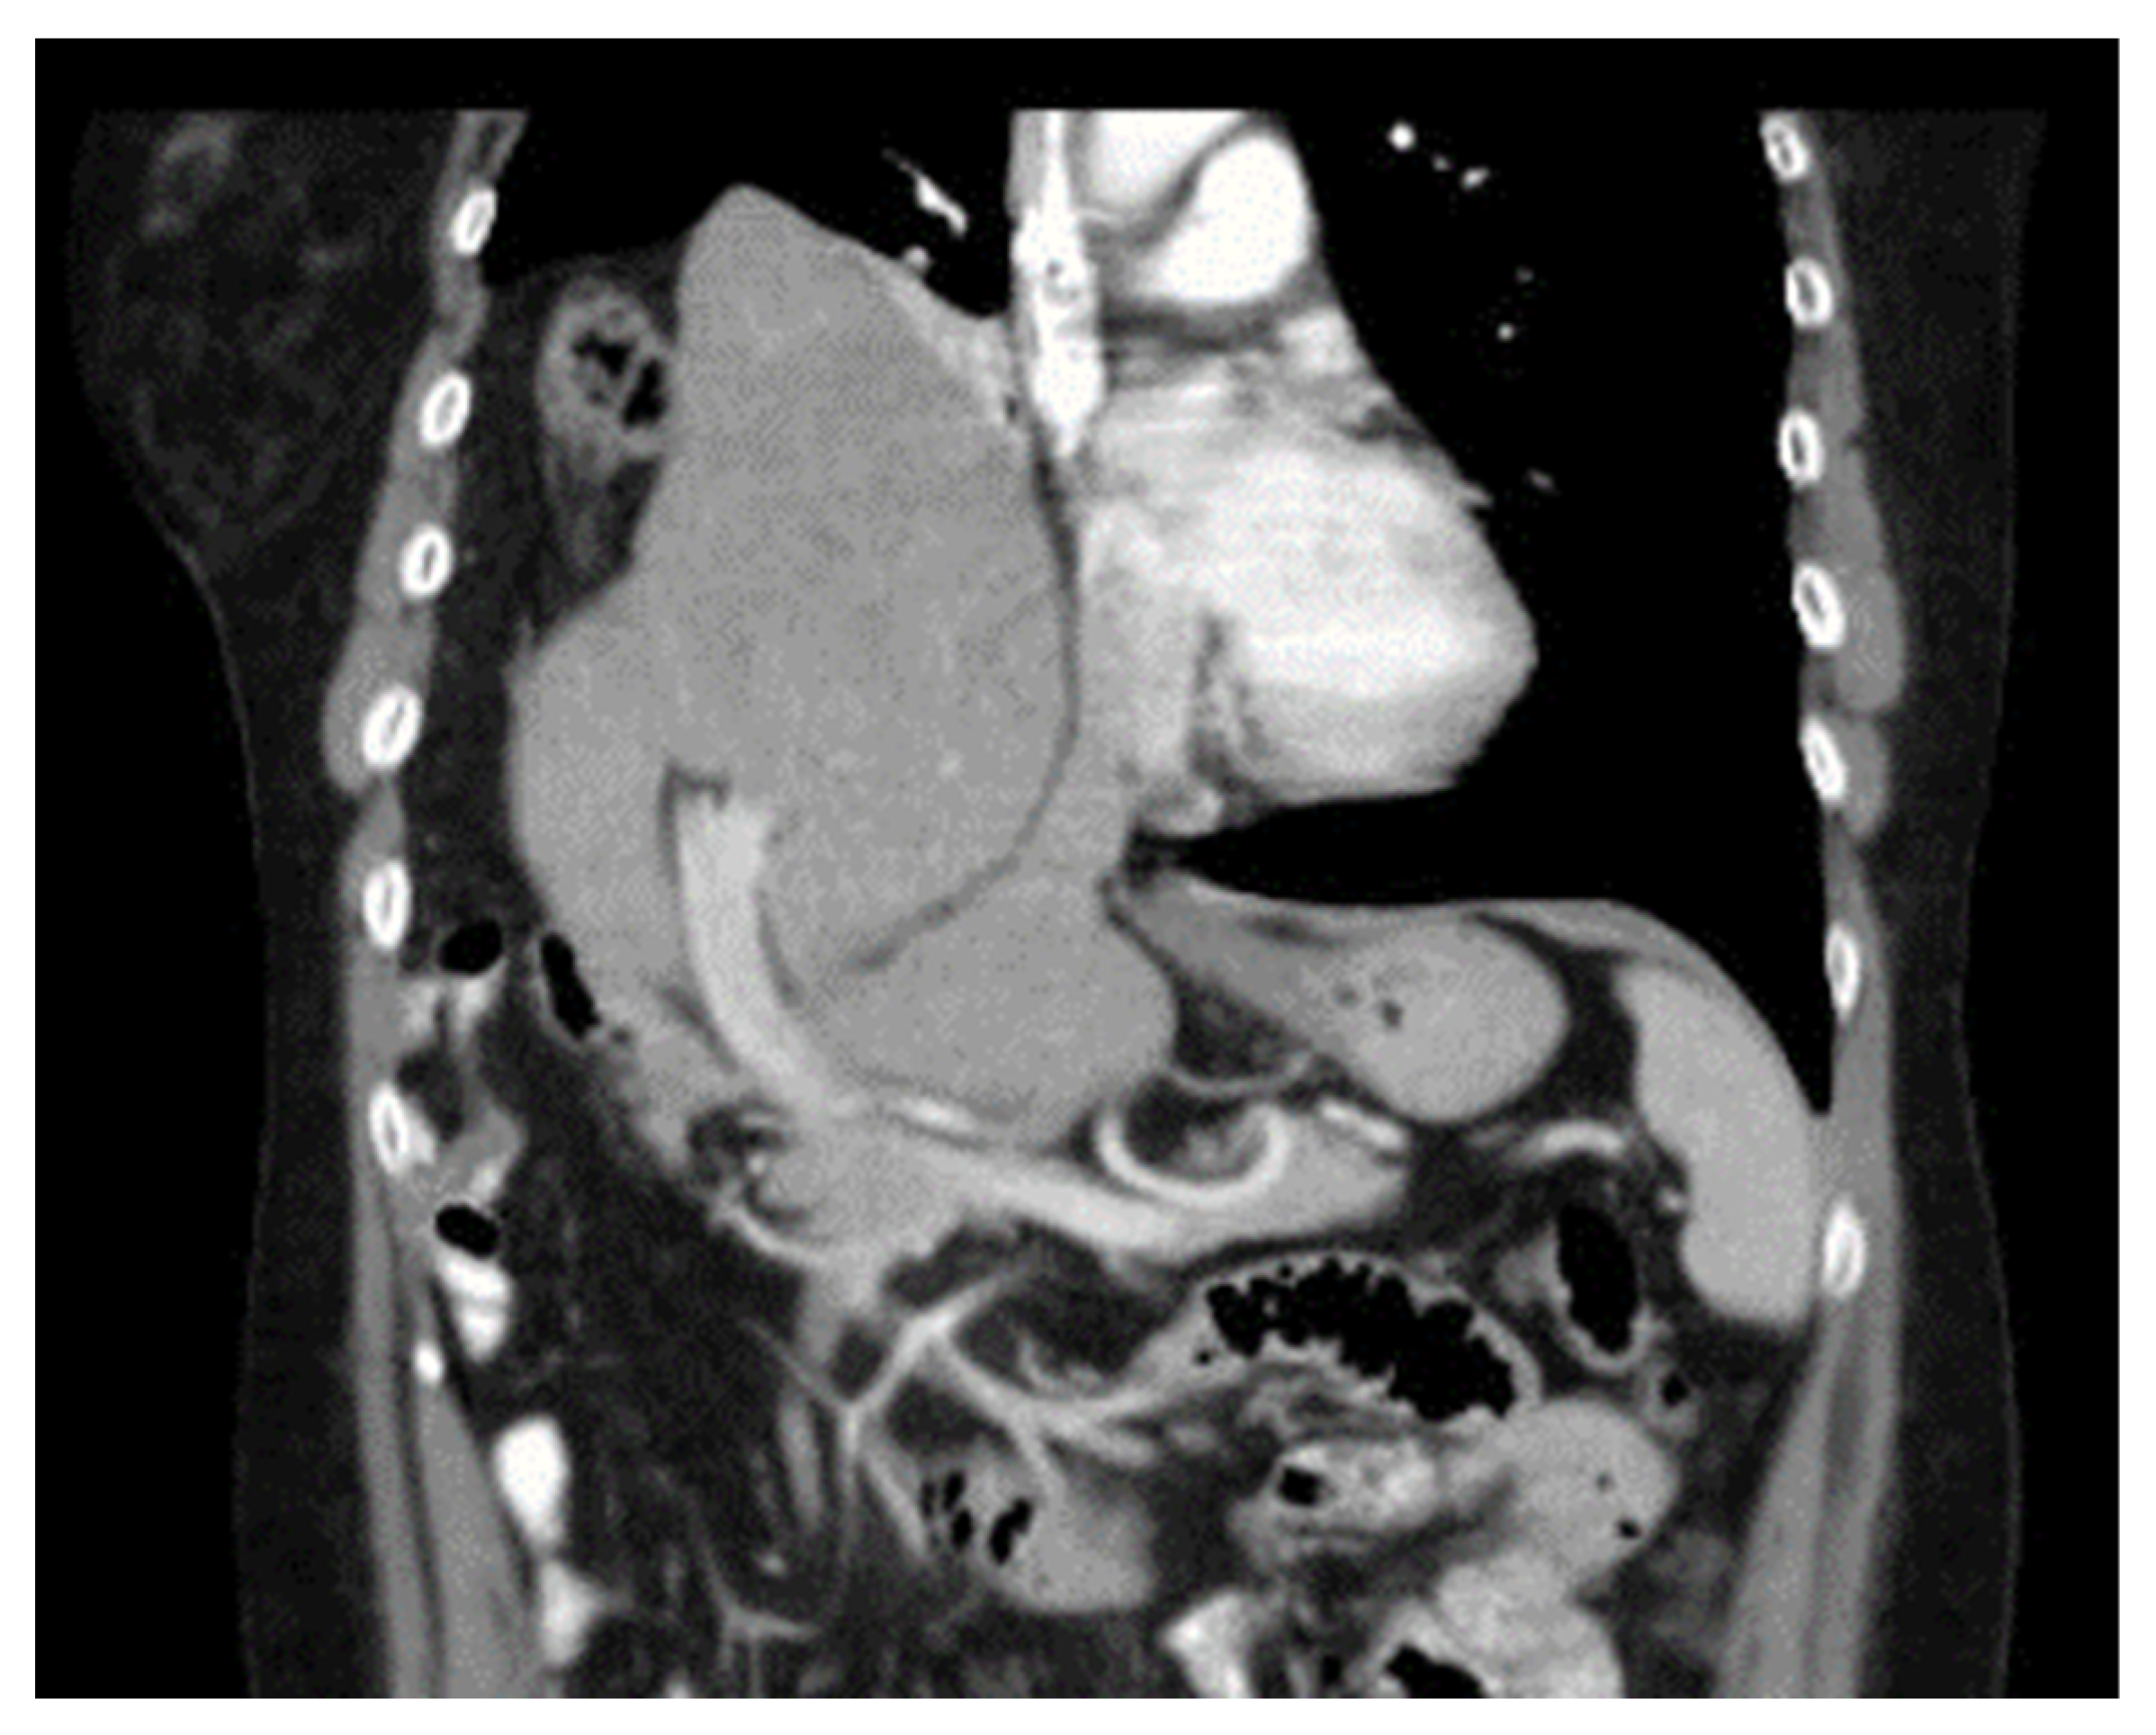

Diaphragmatic Liver Herniation after Radiofrequency Ablation of a Secondary Liver Tumor

Hoskovec, D.; Hořejš, J.; Krška, Z.; Argalácsová, S.; Klobušický, P. Diaphragmatic Liver Herniation after Radiofrequency Ablation of a Secondary Liver Tumor. Diagnostics 2024, 14, 26. https://doi.org/10.3390/diagnostics14010026